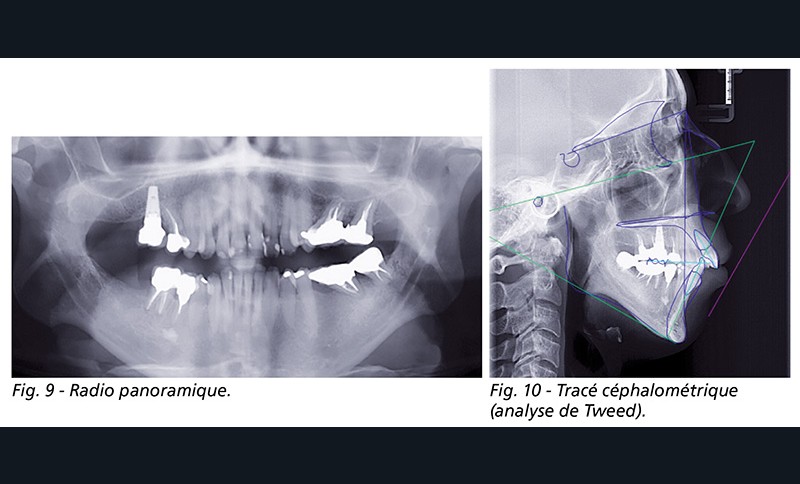

À l’examen fonctionnel, elle présentait une ventilation orale (fig. 9).

Le tracé céphalométrique (analyse de Tweed) montre la forte hyperdivergence, la classe II squelettique sévère et la rétromaxillie et rétromandibulie (fig. 10). À cela, s’ajoute une endomaxillie.